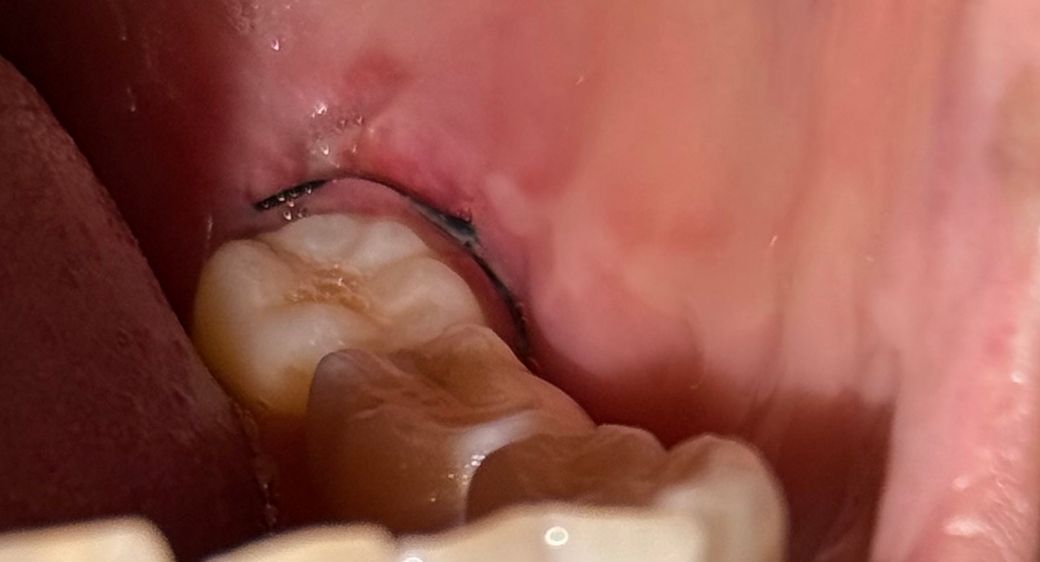

• 2번 째 사진

입 안 보면 잇몸 벽? 쪽에 하얀게 쭉 생겼는데 염증 그런군 아니겠죠......

발치와 관련된 흔적은 아니고 씹어서 생긴 교흔같습니다

통증은 발치 후, 1~2주일까지도 미약하게 있을 수 있습니다